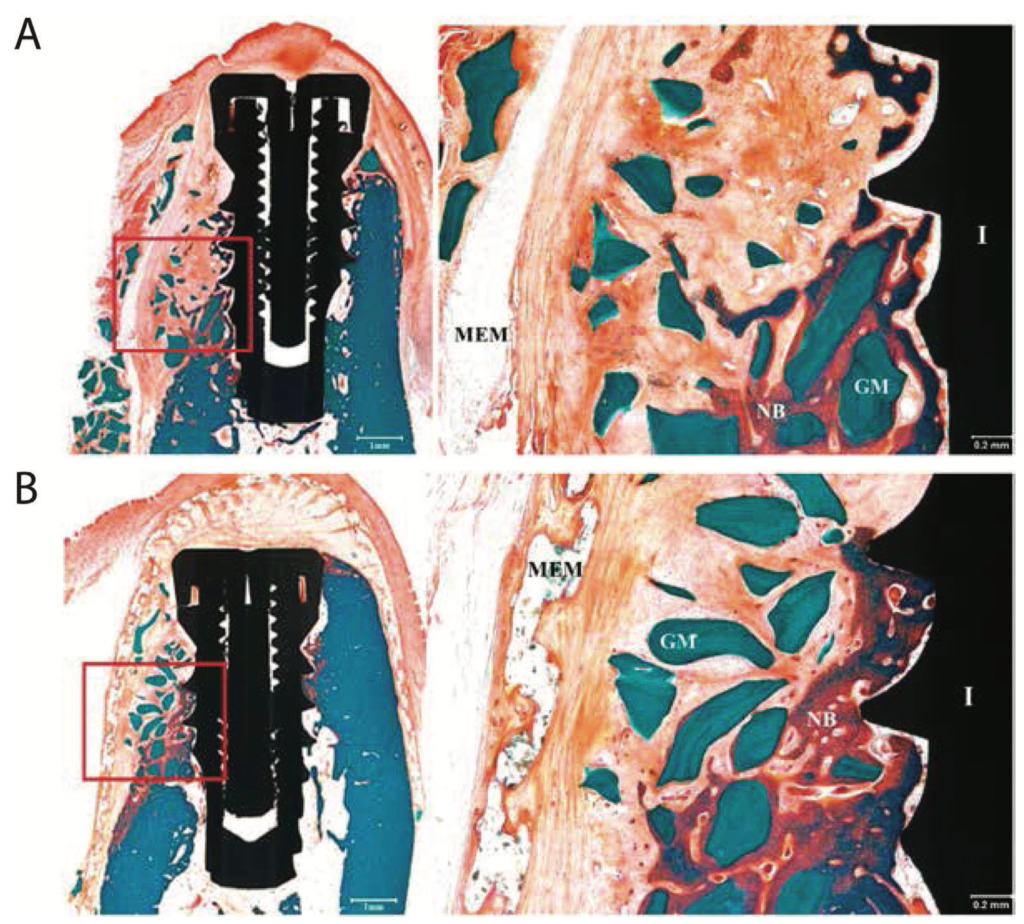

Figure 1 from Barrier Membranes for Guided Bone Regeneration (GBR) A Focus on Recent Advances Barrier Membrane For Guided Bone Regeneration — guided bone regeneration (gbr) is a widely used technique for alveolar bone augmentation. — guided bone regeneration (gbr) has become a clinically standard modality for the treatment of localized. — guided bone regeneration (gbr) is a widely used technique for alveolar bone augmentation. this review, summarizes the evolution of barrier membranes, focusing on the characteristics,. Barrier Membrane For Guided Bone Regeneration.

Figure 2 from Guided Bone Regeneration with AmmoniomethacrylateBased Barrier Membranes in a Barrier Membrane For Guided Bone Regeneration — guided bone regeneration (gbr) is a widely used technique for alveolar bone augmentation. — guided bone regeneration (gbr) has become a clinically standard modality for the treatment of localized. — this review, summarizes the evolution of barrier membranes, focusing on the characteristics, advantages, and. this review, summarizes the evolution of barrier membranes, focusing on the. Barrier Membrane For Guided Bone Regeneration.